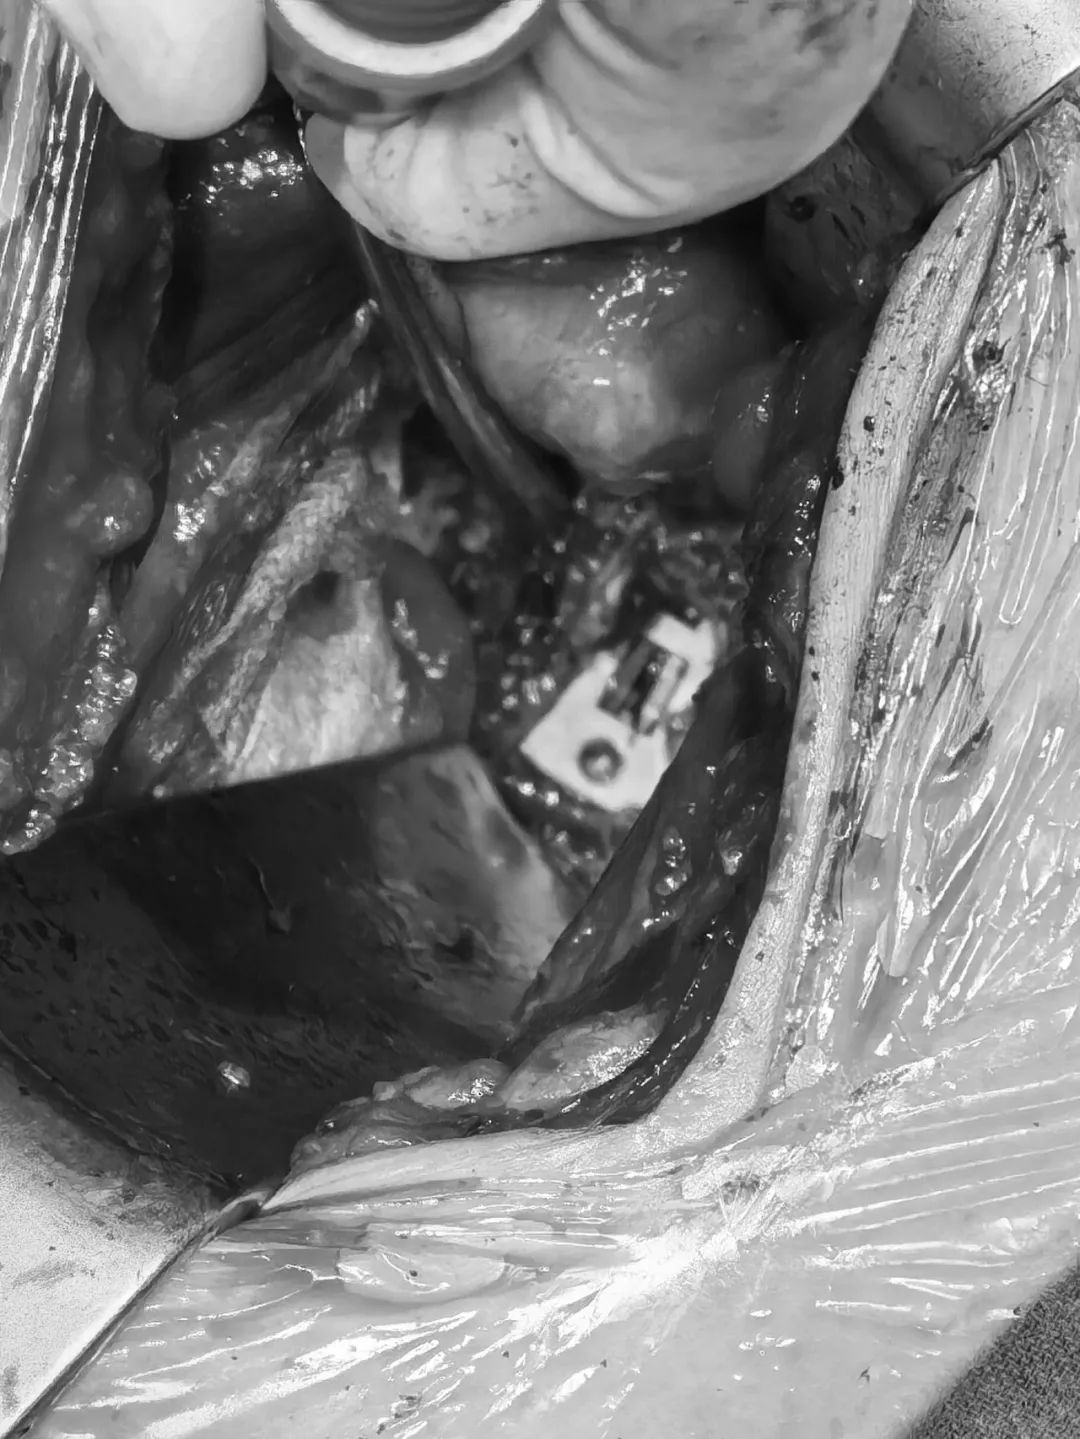

直視圖:cage與固(gu)定夾(jia)完(wan)全打入后

- 固定夾(jia)植入(考慮患者長期不融合,可能存在終(zhong)板硬化。因此,先使用固定夾(jia)開(kai)路器(qi)預(yu)開(kai)路,再植入固定夾(jia))

正視(shi)圖:頭尾側固定夾均已完全打(da)入